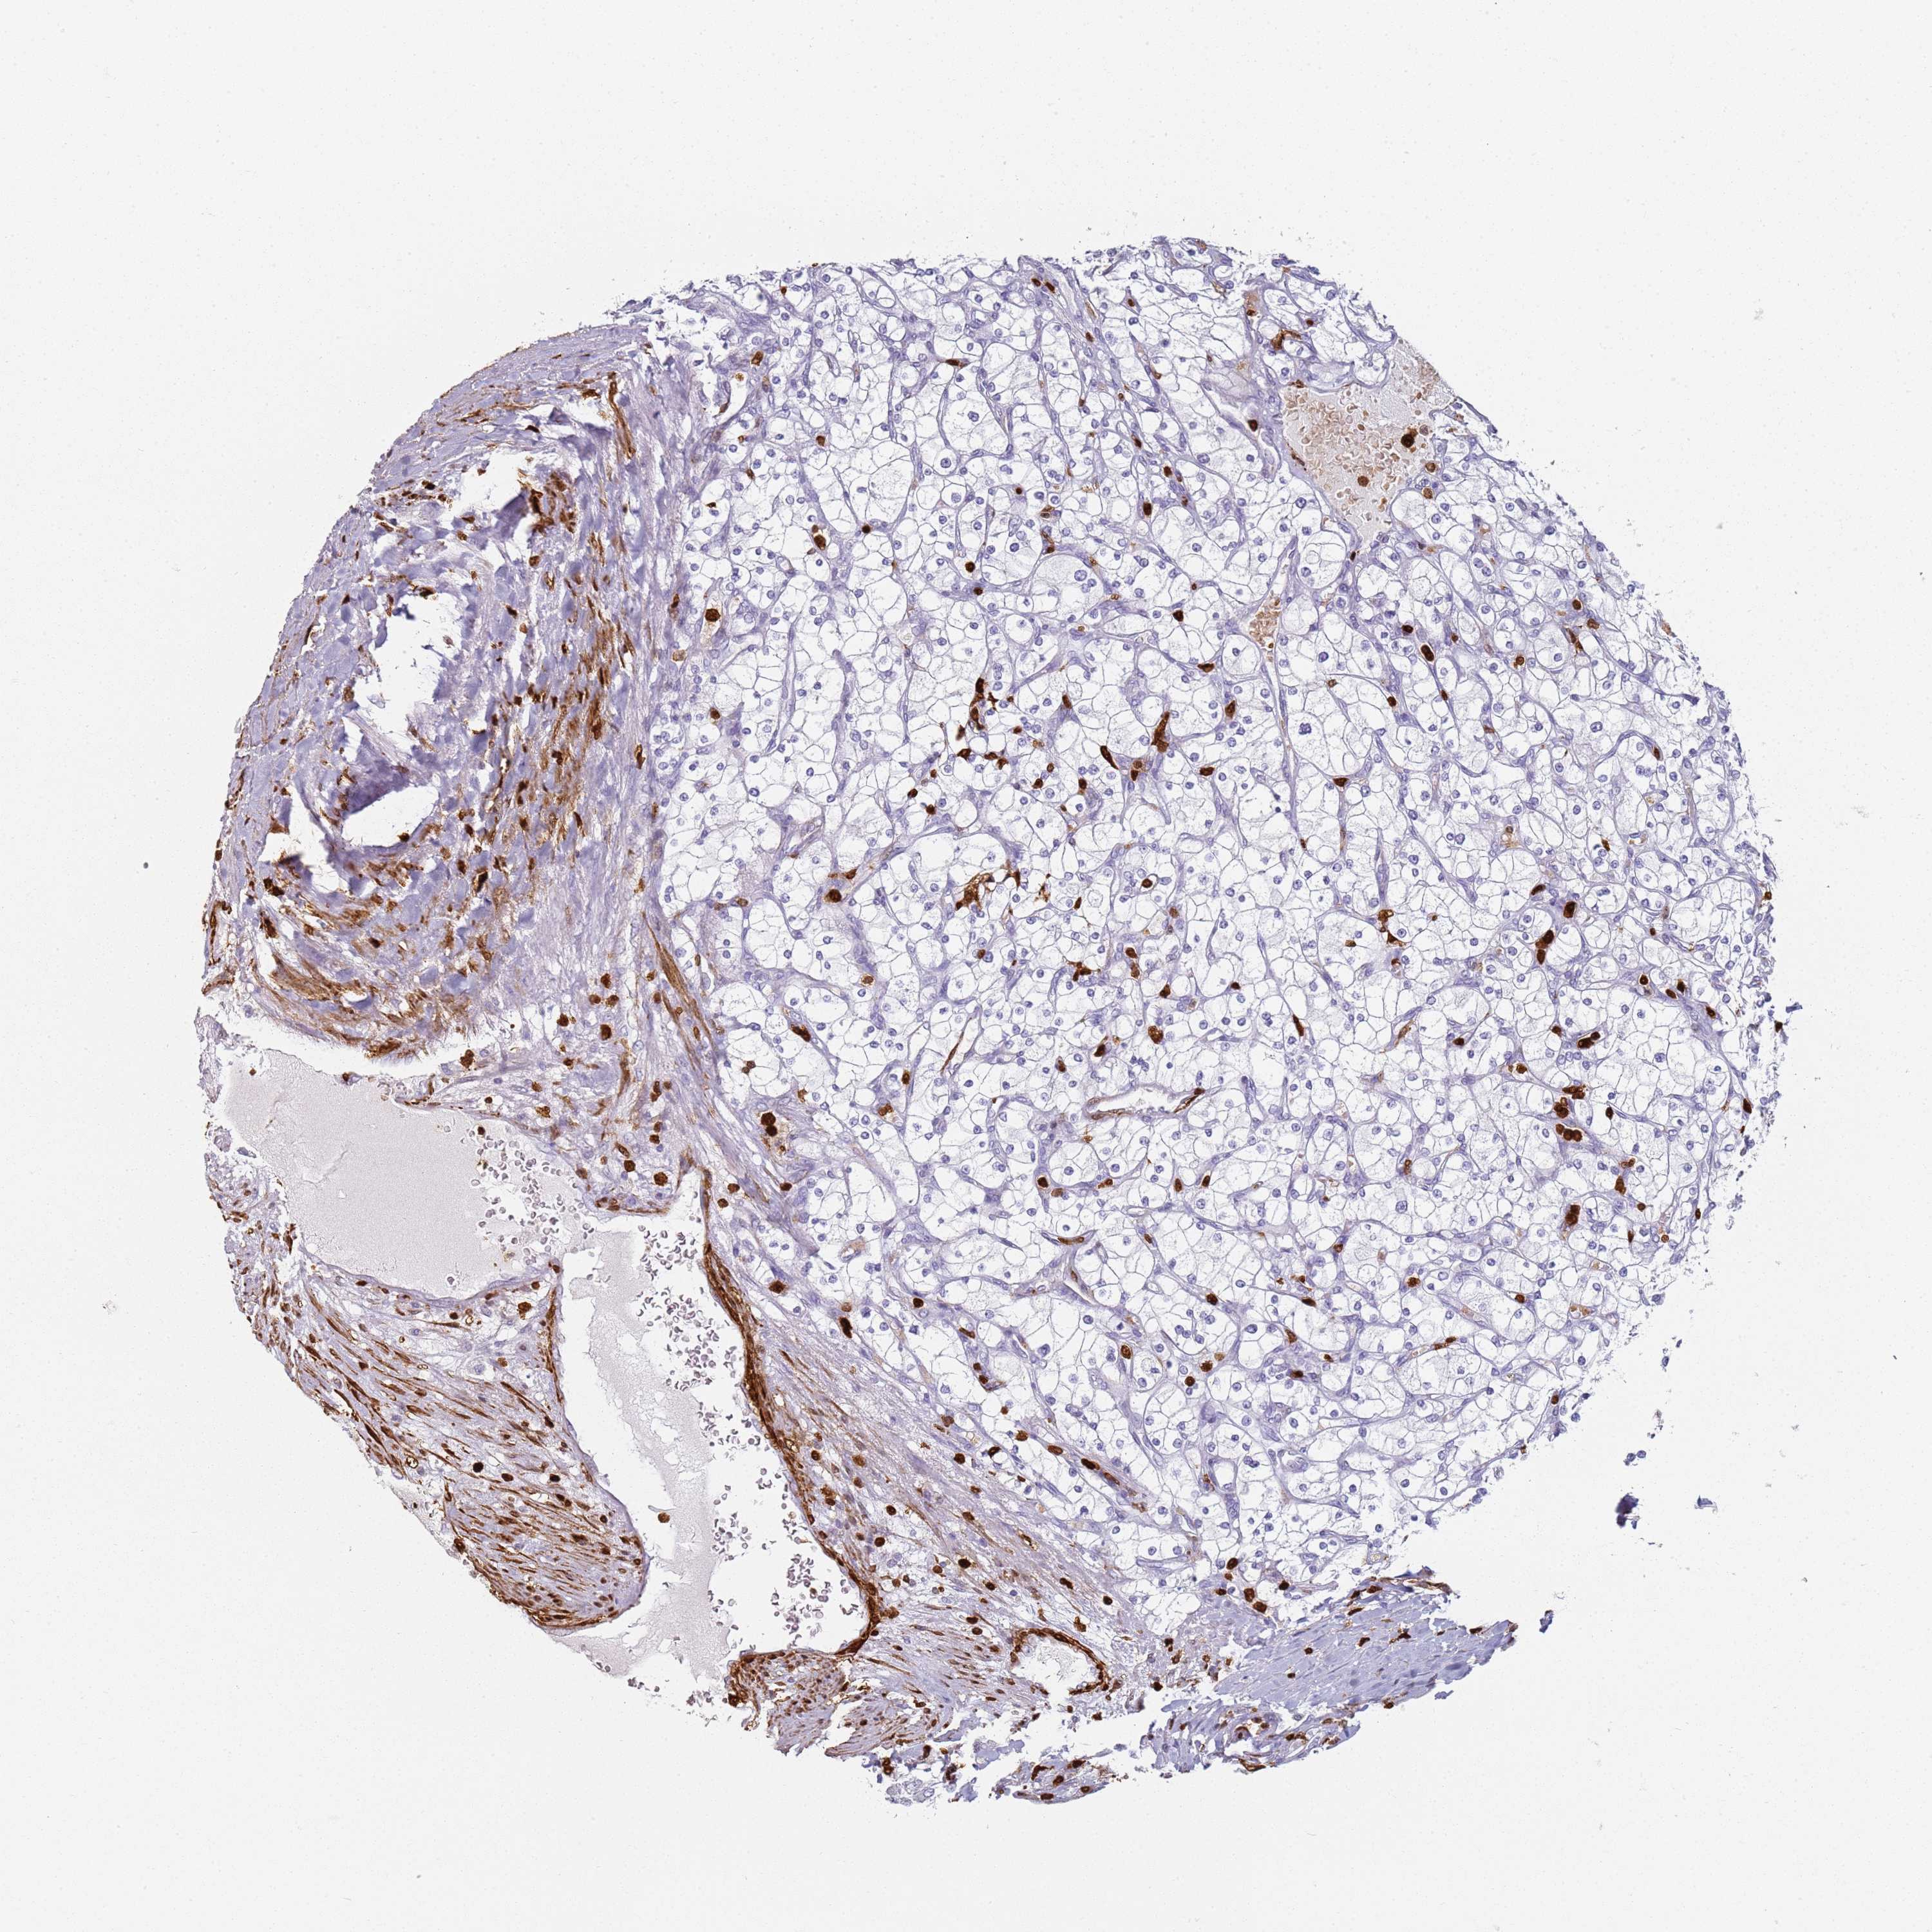

KIDNEY RENAL CLEAR CELL CARCINOMA (VALIDATION) - Interactive survival scatter ploti

The Survival Scatter plot shows the clinical status (i.e. dead or alive) for all individuals in the patient cohort, based on the same data that underlies the corresponding Kaplan-Meier plots. Patients that are alive at last time for follow-up are shown in blue and patients who have died during the study are shown in red.

The x-axis shows the expression levels (FPKM) of the investigated gene in the tumor tissue at the time of diagnosis. The y-axis shows the follow-up time after diagnosis (years). Both axes are complimented with kernel density curves demonstrating the data density over the axes. The top density plot shows the expression levels (FPKM) distribution among dead (red) and alive patients (blue). The right density plot shows the data density of the survived years of dead patients with high and low expression levels respectively, stratified using the cutoff indicated by the vertical dashed line through the Survival Scatter plot. This cutoff is automatically defined based on the FPKM cutoff that minimizes the p-score. The cutoff can be changed by dragging the vertical line or by entering a cutoff value in the square labeled "Current cut-off".

Under the Survival Scatter plot the p-score landscape (black curve; left axis) is shown together with dead median separation (red curve; right axis). Dead median separation is the difference in median mRNA expression between patients who have died with high and low expression, respectively. It is calculated as follows: median FPKM expression of dead patients with high expression - median FPKM expression of dead patients with low expression. This is intended to aid the user in visually exploring custom cutoffs and the associated p-scores and dead median separation.

Individual patient data is displayed and can be filtered by clicking on one or more of the category buttons on the top of the page. Categories describing expression level and patient information include: high, low, alive, dead, female, male and tumor stages. The scale of the x-axis can be toggled between linear and log-scale by clicking on the "x log" button. Mouse-over function shows TCGA ID, patient information and mRNA expression (FPKM) for each patient.

& Survival analysisi

Kaplan-Meier plots summarize results from analysis of correlation between mRNA expression level and patient survival. Patients were divided based on level of expression into one of the two groups "low" (under cut off) or "high" (over cut off). X-axis shows time for survival (years) and y-axis shows the probability of survival, where 1.0 corresponds to 100 percent.

S100A4 is not prognostic in Kidney Renal Clear Cell Carcinoma (validation)

Best expression cut offi

Based on the FPKM value of each gene, patients were classified into two groups and association between prognosis (survival) and gene expression (FPKM) was examined. The best expression cut-off refers the FPKM value that yields maximal difference with regard to survival between the two groups at the lowest log-rank P-value. Best expression cut-off was selected based on survival analysis .

When clicking on this number, the vertical dashed line indicating cut-off, the interactive survival plot, and the Kaplan-Meier curve will be adjusted to show results based on the best expression cut-off.

: 108.1

TCGA RNA samplesi

RNA-seq data is reported as average FPKM (number Fragments Per Kilobase of exon per Million reads), generated by the The Cancer Genome Atlas (TCGA) .

Normal distribution across the dataset is visualized with box plots, shown as median and 25th and 75th percentiles. Points are displayed as outliers if they are above or below 1.5 times the interquartile range. FPKM values of the individual samples are presented next to the box plot.

Average pTPM 173.2

Number of samples 100